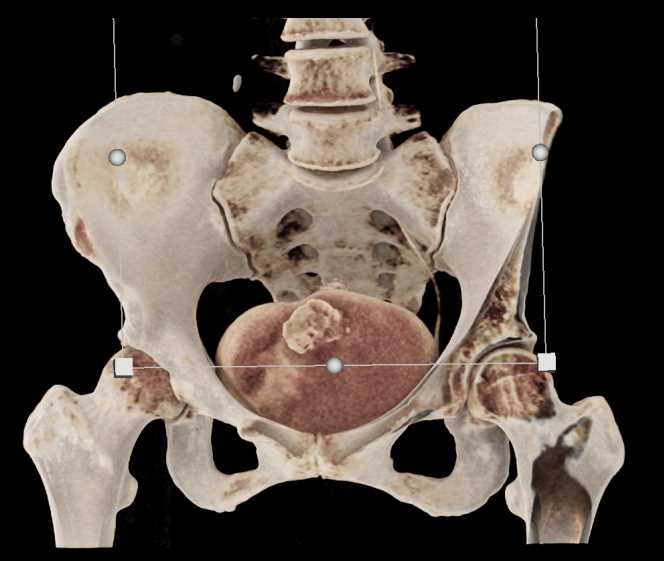

Urachal Carcinoma of the Bladder